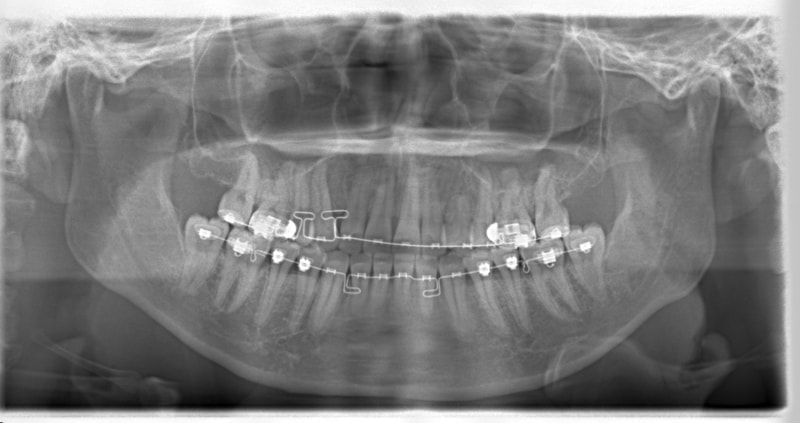

治療法:フルパッシブブラケット:T21

治療開始時